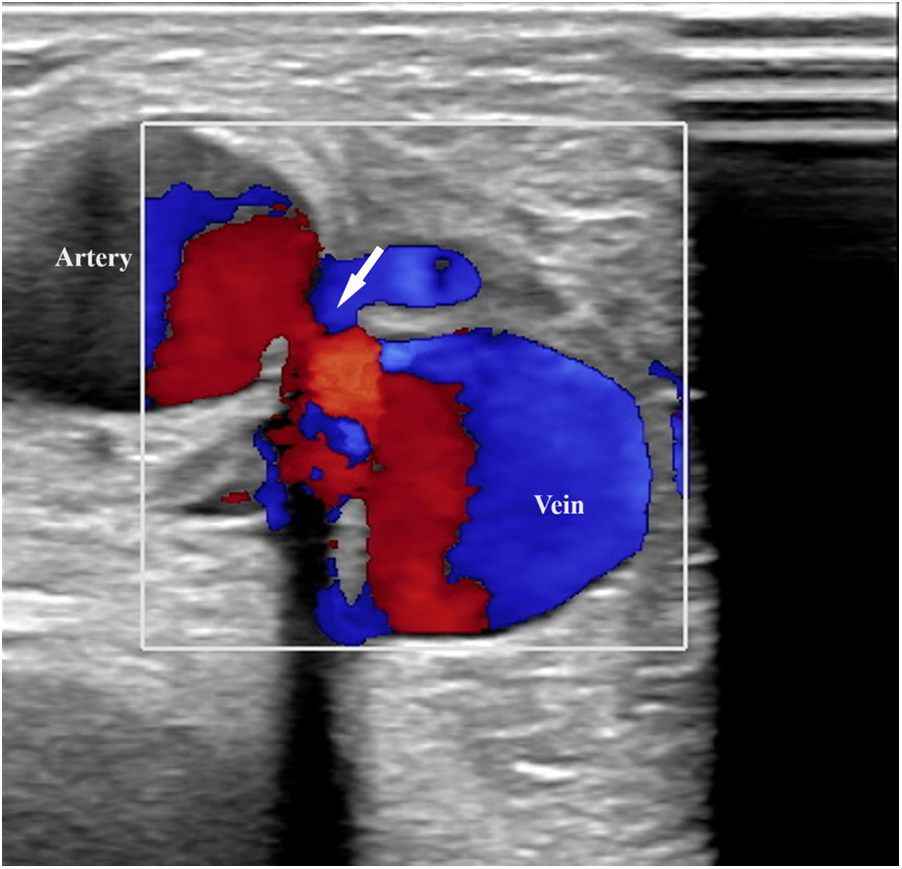

Upon admission to our institute, a CT scan of supra-aortic arteries and ascending and descending aorta was done. A CT scan of supra-aortic arteries revealed a diffusely dilated right axillar artery with a diameter of 19 mm, as well as a 21 × 15 mm aneurysm 46 mm from the vertebral artery's exit. CT scans of the ascending and descending aorta revealed a segmentally calcified ascending aorta with a diameter of 37 mm and arcus aortae with a diameter of 28 mm, as well as an aneurysm of abdominal aorta in the infrarenal segment, measuring 39 mm in diameter and 95 mm in length. CT scans reveal the existence of an arteriovenous fistula in the brachial artery (Figure 2). Doppler sonography of the right arm was performed, which was collaborated with CT findings of the same arm, the presence of an arteriovenous fistula (in the middle) on the inner side of the upper arm, and the presence of an arteriovenous fistula in the cubital fossa in an ulnar artery projection (Figure 3). Due to severe coronary disease, unprotected left main, and three-vessel disease, the heart team recommended surgical revascularization of the left and right system of coronary arteries. Standard on-pump CABG surgery in general anesthesia was done, with central cannulation of the aorta and through the right atrium. The anterograde infusion of cold blood del Nido cardioplegia stopped the heart. The surgical team decided on the use of a free mammary artery graft for LAD revascularization due to AV communication, and suspicion of steal syndrome. The right coronary artery and circumflex coronary artery were revascularized using a saphenous vein graft.

Figure 3

Doppler sonography of the right arm revealed an arteriovenous fistula (in the middle) on the inner side of the upper arm.